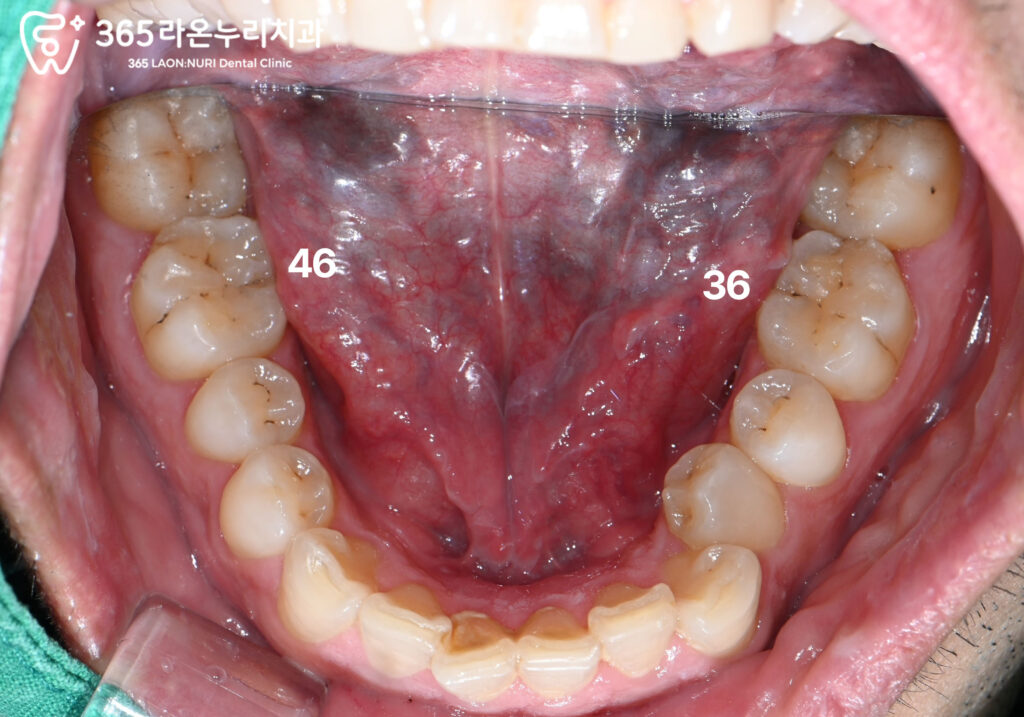

치료가 필요해 보이는 치아들

구강 내에서 갈색으로 보이는 부위가 있다면

이는 대부분 우식일 가능성이 높습니다.

신장동 치과 에서 치식을 적어놓은 부분이

오늘 치료를 할 부위이며,

각각 어떤 치료가 필요한지 알기 위해

엑스레이 촬영을 통해 살펴봅니다.